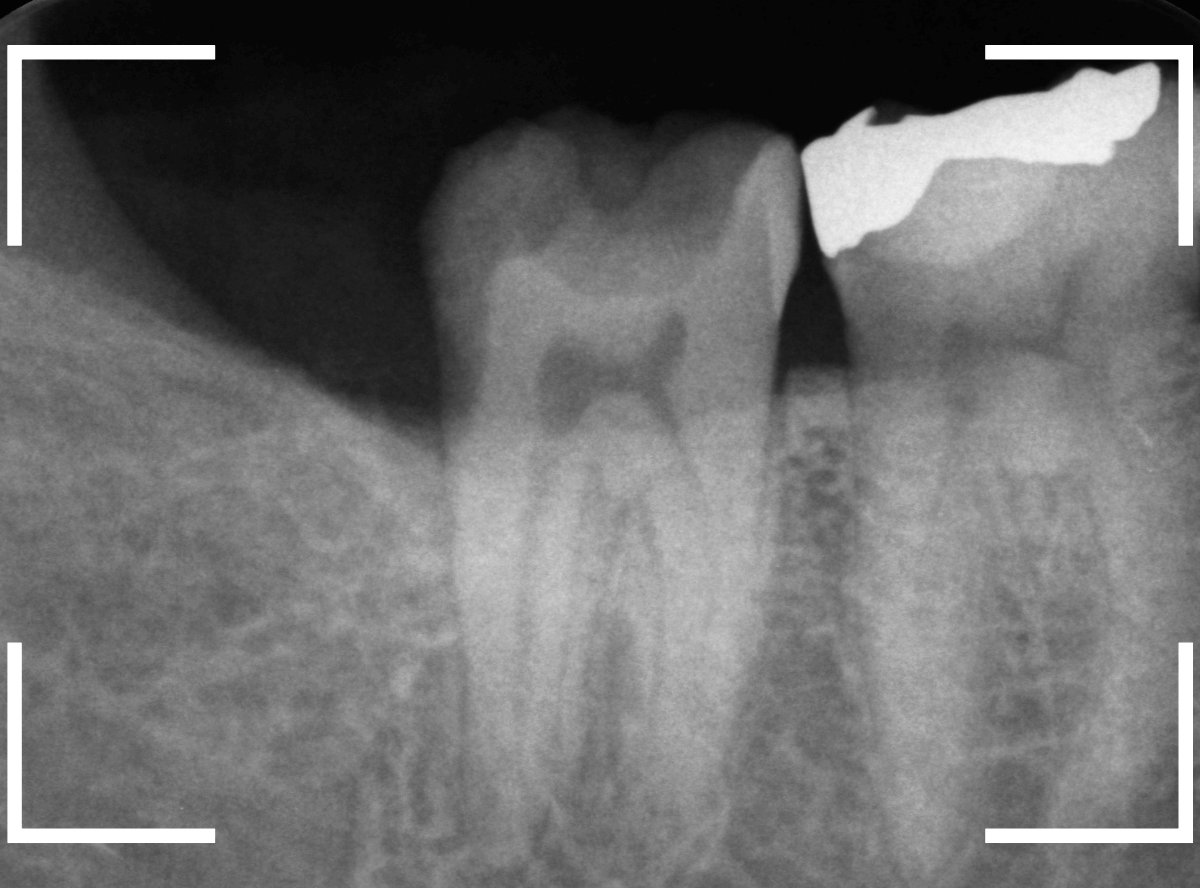

レントゲン写真で確認します。

青いラインが歯の神経、赤いラインが虫歯です。

歯の奥の見えない部分から、大きな虫歯になっているのがわかります。

神経を除去しなければいけないかもしれないくらいの虫歯です。